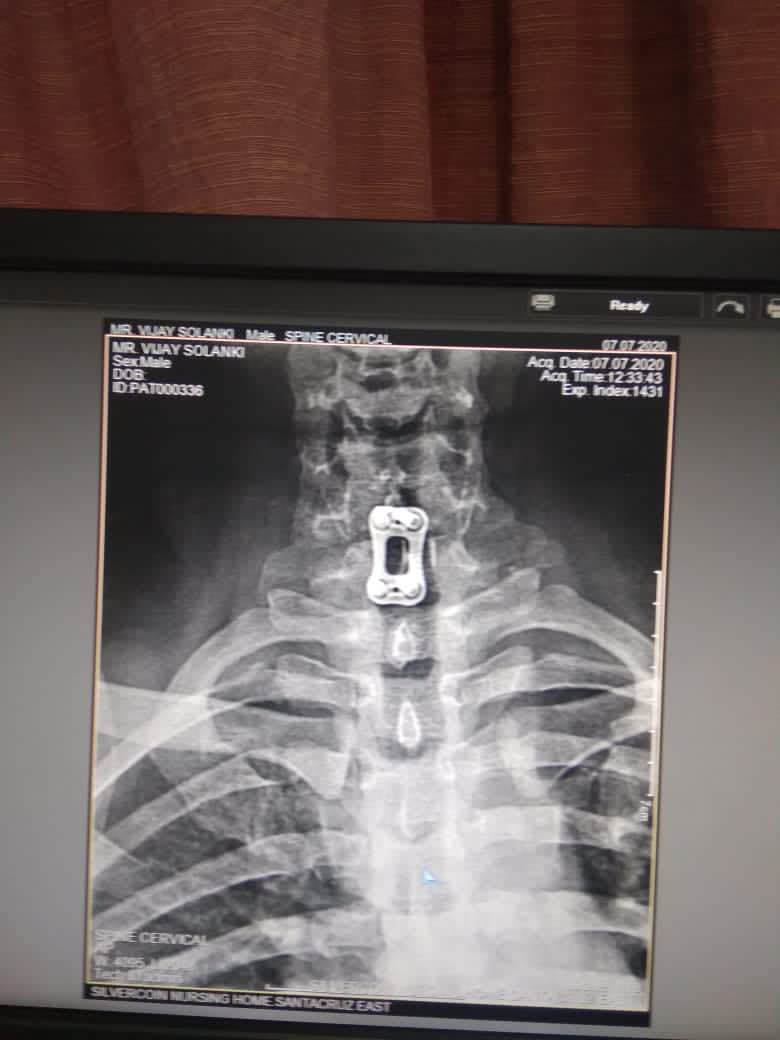

Best SPINE SURGEON in Andheri